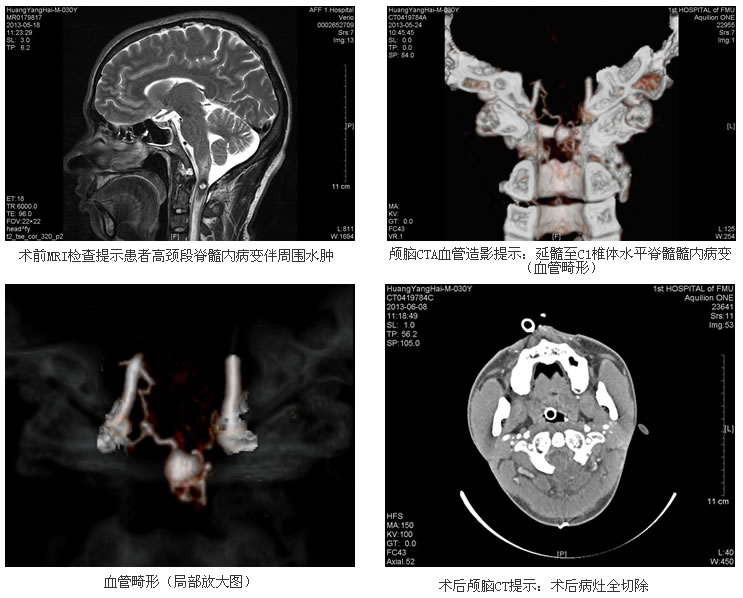

来自红色革命老区的年青小伙黄某刚过而立之年,是一名建筑工人。今年五月初的一天突然出现左肩颈部疼痛,起初以为是挑担子造成的肌肉扭伤,在当地乡镇卫生院服药、推拿治疗十余天,疼痛非但不见好转反而越来越剧烈,随即到该县医院就诊,没想到止痛针还没打完,即出现皮肤瘙痒、人事不醒等过敏性休克反应,并逐渐出现左手不听使唤,进而发展到全身四肢无力、脖子以下完全失去知觉,小便无法自解。原来能挑200斤担子的壮实小伙就这样瘫在床上无法动弹,让这个原来就贫困的家庭蒙上了一层阴影。当地医院做了头部及颈部CT检查没发现异常,无法明确诊断,更让家属一时间手足无措。经多方打听,患者及家属怀着希望转诊至我院,急诊联系了头颅及颈部MRI检查,结果提示“颈髓病变”,考虑脊髓炎症或海绵状血管瘤并出血,随收入神经内科诊治。患者病变位于高颈段脊髓内,周围水肿明显,波及控制呼吸的生命中枢——延髓,随时有出现呼吸、心跳骤停的可能。医疗组按照标准治疗方法给予激素冲击、药物脱水、辅以营养神经、营养等支持治疗,但患者病情仍不见好转,并逐渐出现呼吸困难、急促,离呼吸停止只有一步之遥。病情的恶化让患者家属心底最后的一丝希望也面临破灭。然而,病情的复杂并没有把医生难倒,经神经内科、神经外科与影像科专家共同会诊,在对患者进行颅脑CTA检查后,将诊断锁定于“颈1水平椎管内血管畸形并出血”。在疑似山穷水尽之际,患者转到了我院神经外科。

常务副院长、神经外科主任康德智教授、林元相主任医师带领医疗组接诊后,立即组织全科多次讨论,并组织介入组专家对患者进行最新的三维DSA血管造影术,确认患者系颈1脊髓内血管畸形,是一种少见且危险的血管性病变。因为病灶及水肿带离延髓呼吸中枢只有不到1毫米的距离,如果继续发展,患者随时都可能出现呼吸无力甚至停止、死亡,手术风险极大。据国内外文献报道,该区域的手术术后出现呼吸功能衰竭,需长期靠呼吸机辅助呼吸的几率很高,但手术切除是治疗该病的唯一手段。经过多次沟通,患者及家属理解并要求行手术治疗。

经过充分的术前准备,康德智常务副院长、林元相教授等手术组专家运用目前国内先进的术中电生理监测和术中荧光造影技术,在显微镜下沿颈1脊髓后正中纵向切开1.5cm,以娴熟精湛的手术技巧,成功将被包在脊髓内部约花生米(1.2cm×1.0cm×0.8cm)大小的血管畸形团完整切除。病理结果回报确诊为血管畸形。术后患者神志清楚,完全自主呼吸,摆脱了“断气”的魔咒。随着术后精心的照顾和治疗,患者的四肢和上部躯干也逐渐恢复知觉,目前正在进一步的康复之中。